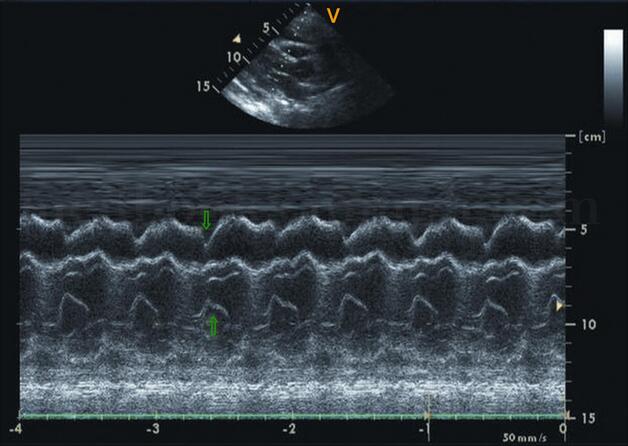

图2‐1‐228 大量心包积液

A﹒显示心尖部积液,厚度达35mm;B﹒左室短轴切面;C﹒大量心包积液使右室前壁受压塌陷;D﹒大量心包积液使右房壁受压塌陷PE:心包积液